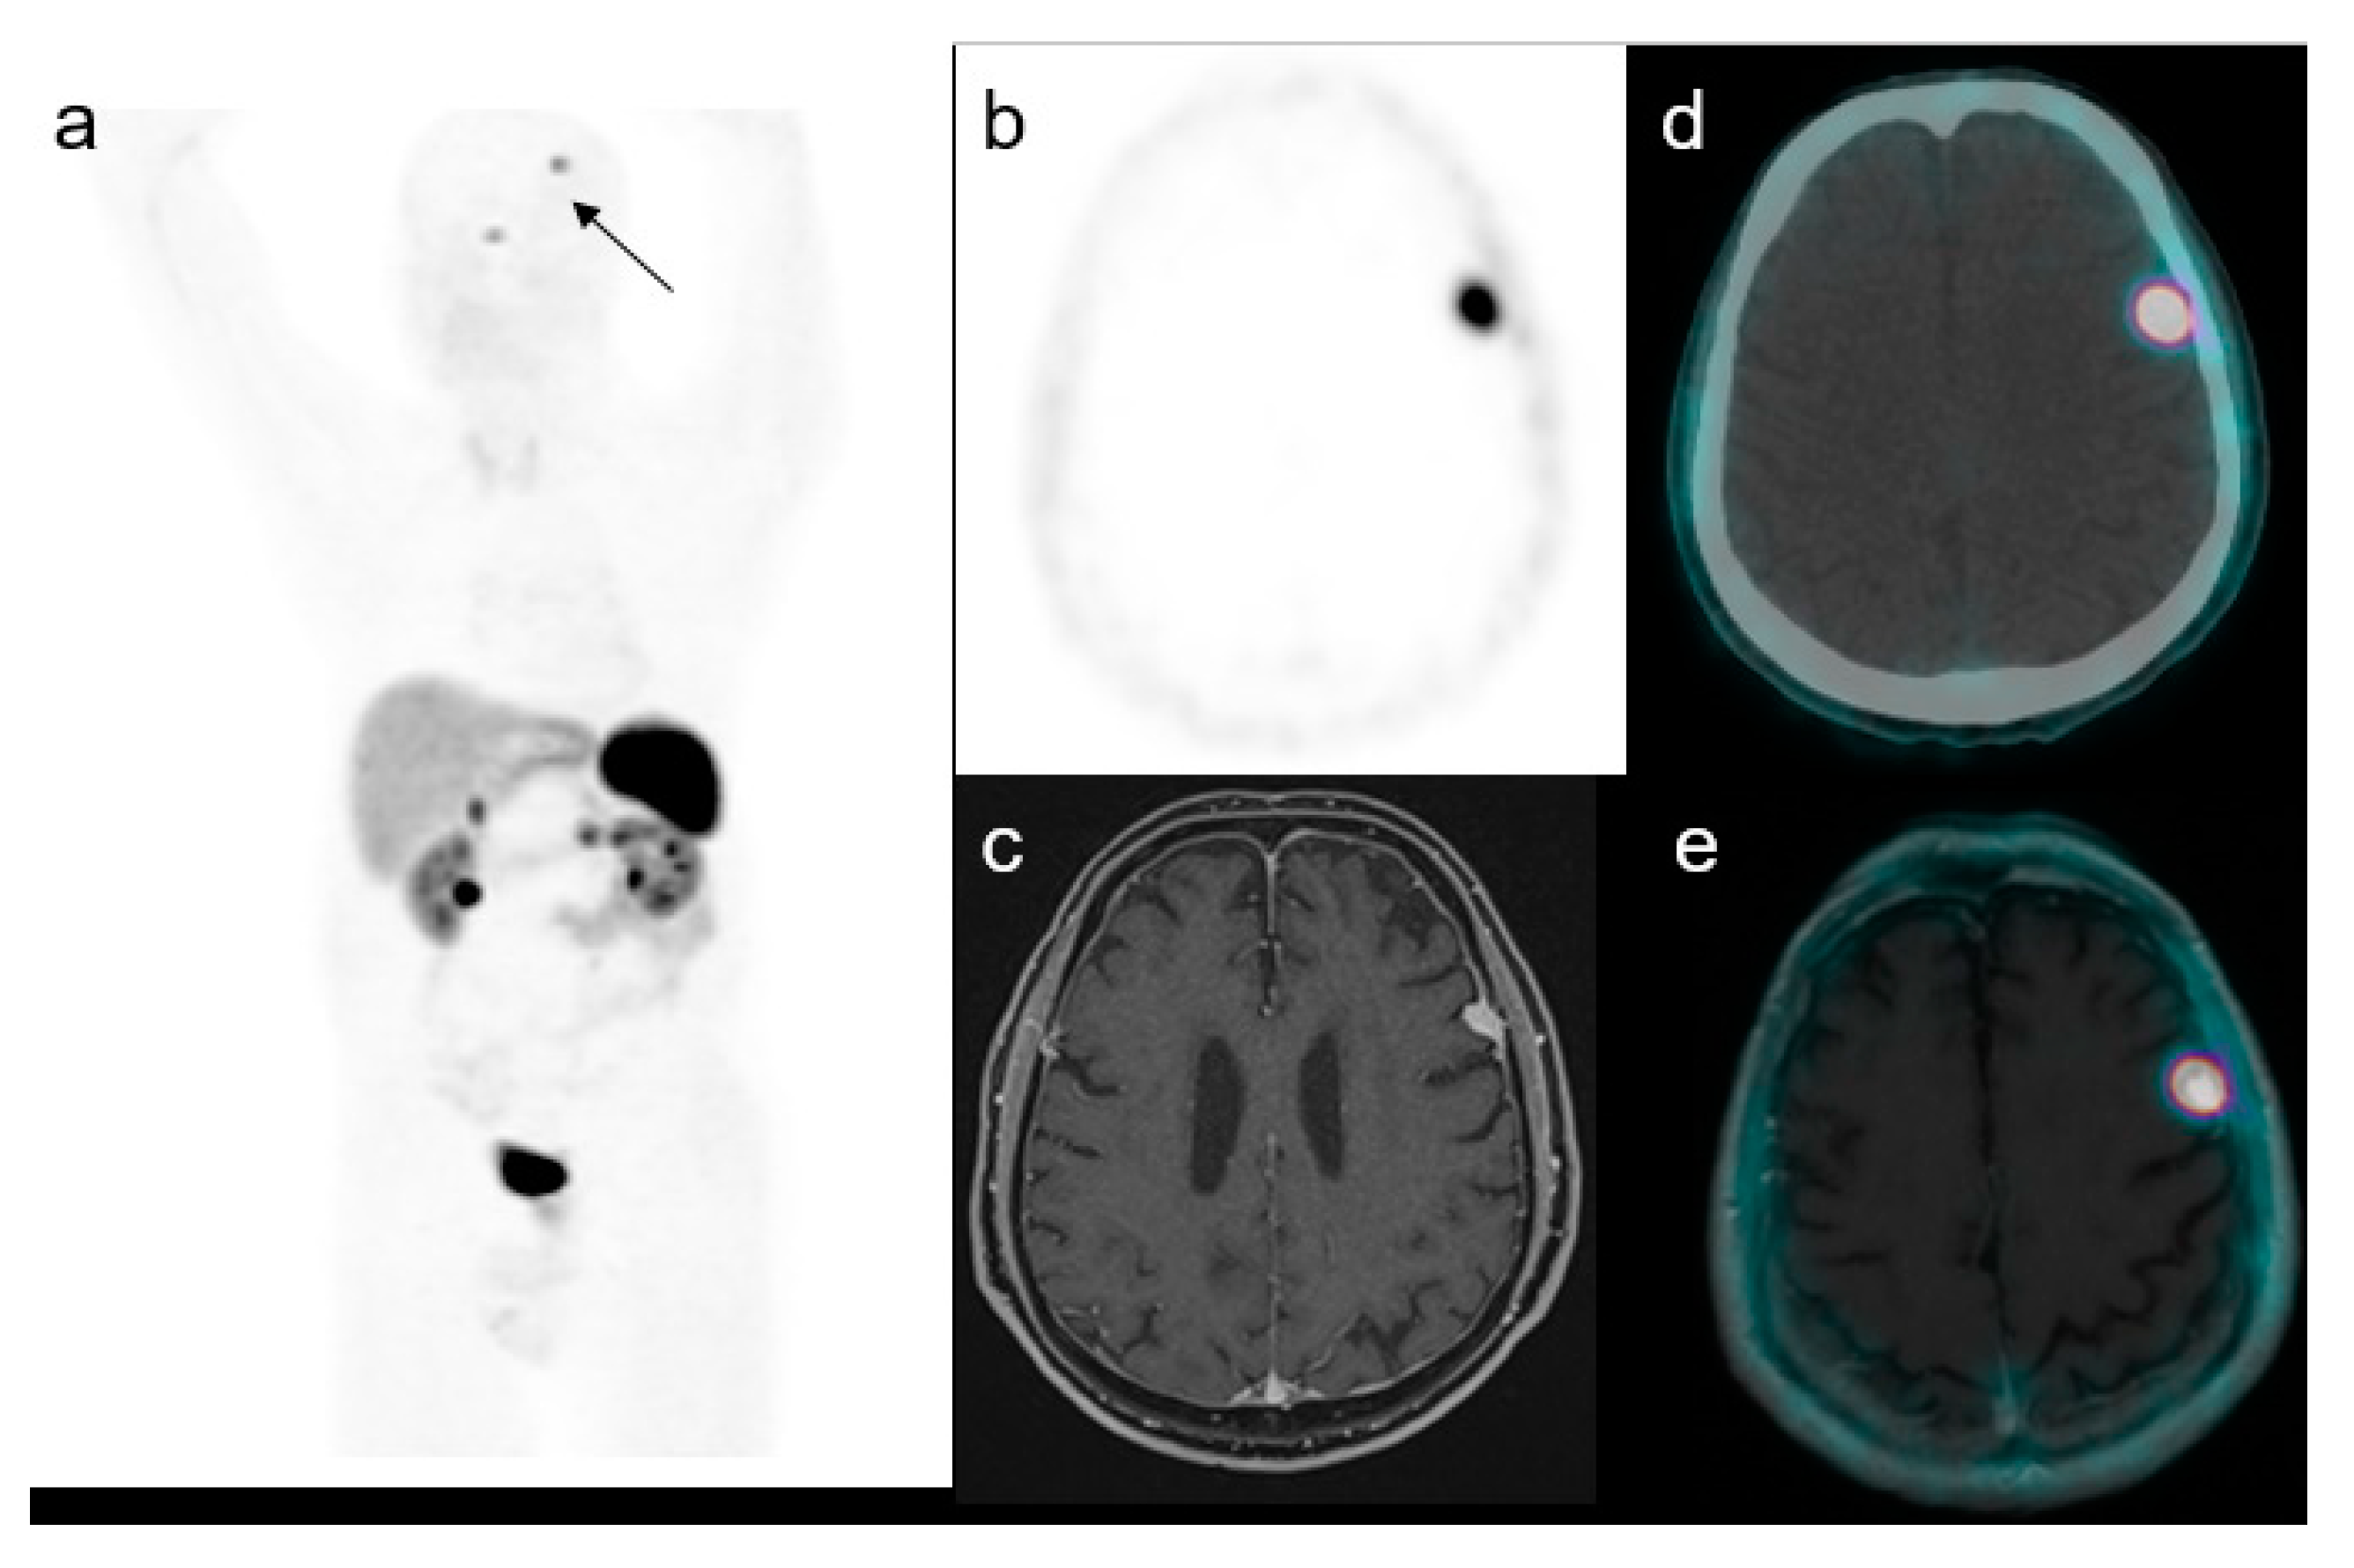

Figure 2.

A representative case of a 59-year-old male with an increased uptake in the brain on the left side at maximum intensity projection (MIP, (a)). Axial PET (b), MRI (c), PET/CT fused (d) and PET/MRI fused images (e) confirmed the presence of a focal uptake in the left frontal region with a SUVmax of 17.5 confirmed to be a meningioma.